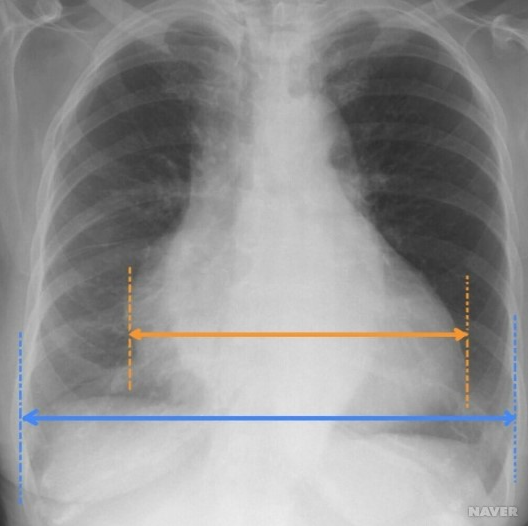

6. 흉부 엑스레이 (Chest X-ray)

흉부 엑스레이는 고혈압성 심근증에서 발생할 수 있는 폐부종(폐에 체액이 고인 상태)이나 심장 비대를 확인하는 데 사용됩니다.

- 심장 크기: 엑스레이를 통해 심장의 크기가 커졌는지 확인할 수 있습니다. 고혈압성 심근증에서는 좌심실 비대에 의해 심장의 크기가 커질 수 있습니다.

- 폐부종: 폐에 체액이 축적되어 있는지 확인할 수 있습니다. 이는 심장의 펌프 기능 저하로 인해 발생할 수 있는 문제입니다.